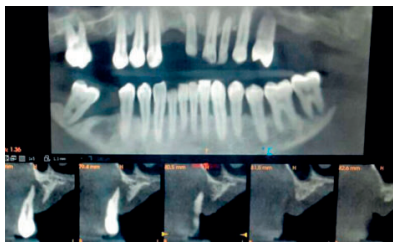

Tras la valoración radiográfica, el paciente queda diagnosticado con edentulismo parcial maxilar con atrofia de procesos alveolares. En primer lugar, se inicia el tratamiento del cuadrante superior izquierdo, donde se observa una reabsorción de la cresta residual, correspondiéndose con la clase SA-3 subdivisión B de la clasificación subantral de Misch de 1987 (5-10 mm de hueso vertical y poco hueso en achura entre el suelo antral y la cresta del reborde residual)9 (Figura 1).

Antes de iniciar la regeneración, se comienza con la exodoncia del primer premolar superior izquierdo por su pronóstico desfavorable a corto plazo. Tras la cicatrización postextracción transcurridos dos meses, se puede observar una cresta alveolar remanente de apenas 6 mm de altura (Figura 2).